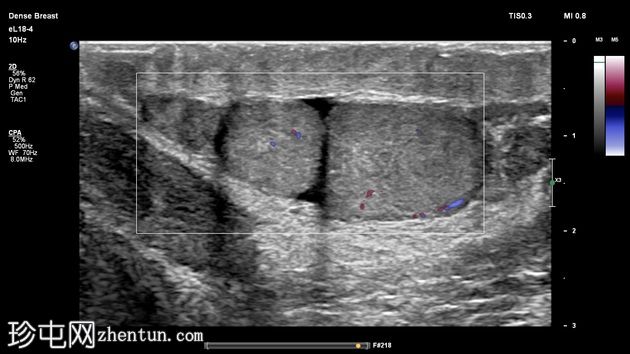

两个睾丸回声和血流均正常,内部未见病变,但患侧可见少量鞘膜积液。

右侧睾丸大小、回声和血流均正常,内部未见病变,体积为4毫升。其附睾正常,未见鞘膜积液。